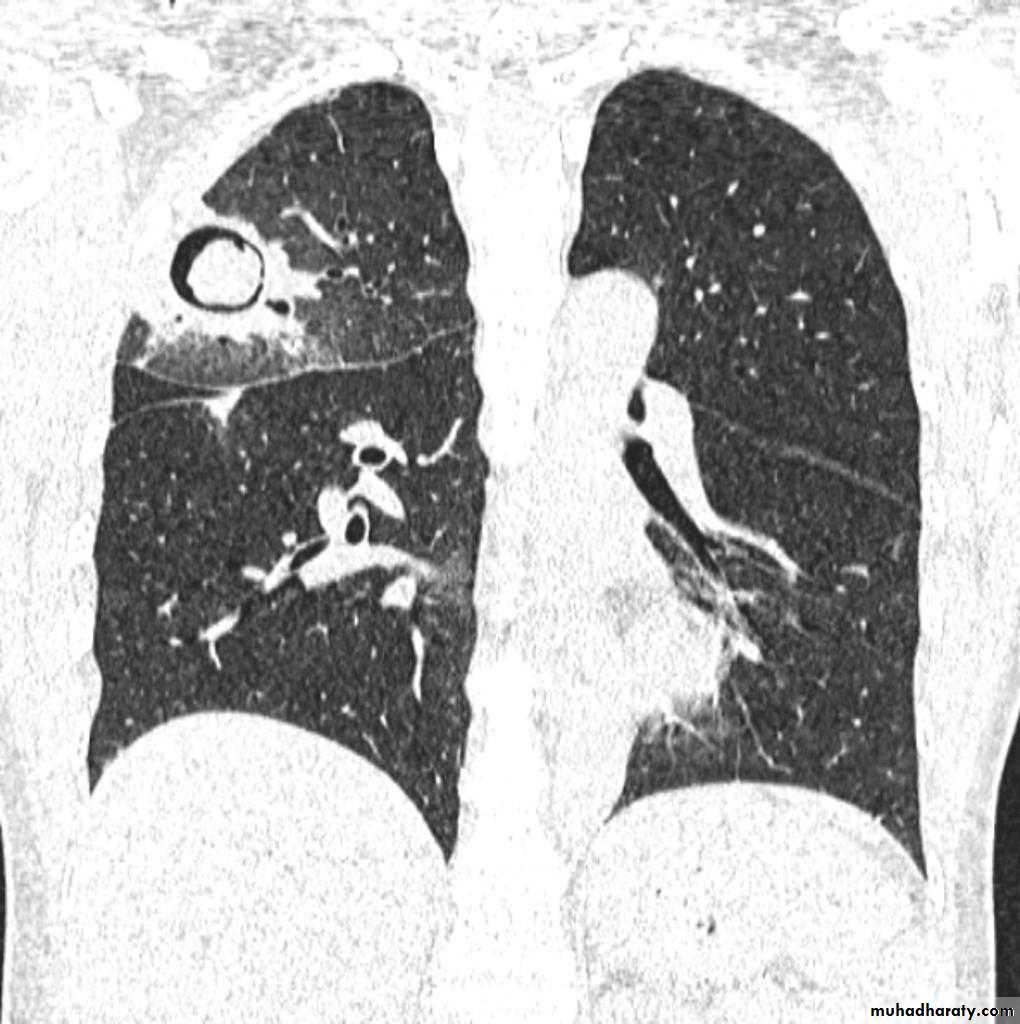

TB abscess

1.patchy consolidation or poorly defined linear and nodular opacities in both apices , upper zone in one lung , & lower zone in other lung ( ulternating lesion ) .2. Post-primary infections are far more likely to cavitate with multiple abscess formation & air fluid level more develop in the posterior segments of the upper lobes.

3. Tuberculomas seen in post-primary TB and appear as a well defined rounded mass typically located in the upper lobes .

Recognized complications include:1.colonisation of cavities by fungus, e.g. HYPERLINK "http://radiopaedia.org/articles/aspergilloma" aspergilloma